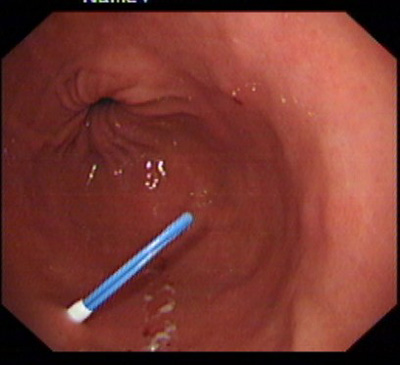

在消化科董蕾主任关心和指导下,消化科王进海教授,张利医师成功地给一位脑出血后吞咽困难的患者实施了经皮内镜下胃造瘘术。

该患者系男性,76岁,脑出血后留有吞咽困难后遗症,不能自主进食,需长期留置胃管供给营养,严重的影响了病人的生活质量和原发病的恢复。经皮内镜下胃造瘘术(Percutaneous endoscpic gastrostomy,PEG)是一种无需常规外科手术和全身麻醉的造瘘技术,可以在胃镜室或病房局麻下进行,因此是一种操作简便、创伤小、安全可靠的方法。该例患者在胃镜室局麻下进行手术,手术过程约10分钟,术后病人无明显不适,3天后即可从造瘘管给食物并出院。

该手术的成功填补了院内空白,丰富了内镜下治疗的内容。对于各种原因造成的长期或较长期不能(一月以上)经口进食者,可通过造瘘管供给病人足够的营养物质,效果优于传统的鼻胃管饲营养,费用又明显低于静脉内营养,是一项值得推广的内镜下较为安全的治疗技术。经皮内镜下胃造瘘术适应证包括:①中枢神经系统或全身性疾病导致的吞咽困难或不能吞咽。如:脑干炎症、变性,脑血管意外,脑肿瘤, 脑外伤;急性呼吸衰竭;系统性硬化症、重症肌无力;完全不能进食的神经性厌食或神经性呕吐导致严重的营养不良,而不能耐受手术造瘘者;②口、咽、喉手术前后及头颈部肿瘤放疗期间,需较长时间营养支持者。③食管广泛瘢痕者;④严重的胆外瘘需将胆汁引回胃肠道者;⑤各种原因所致呼吸功能障碍须气管切开,同时需PEG者;⑥胃肠减压(一月以上的鼻胃管留置者)的目的。